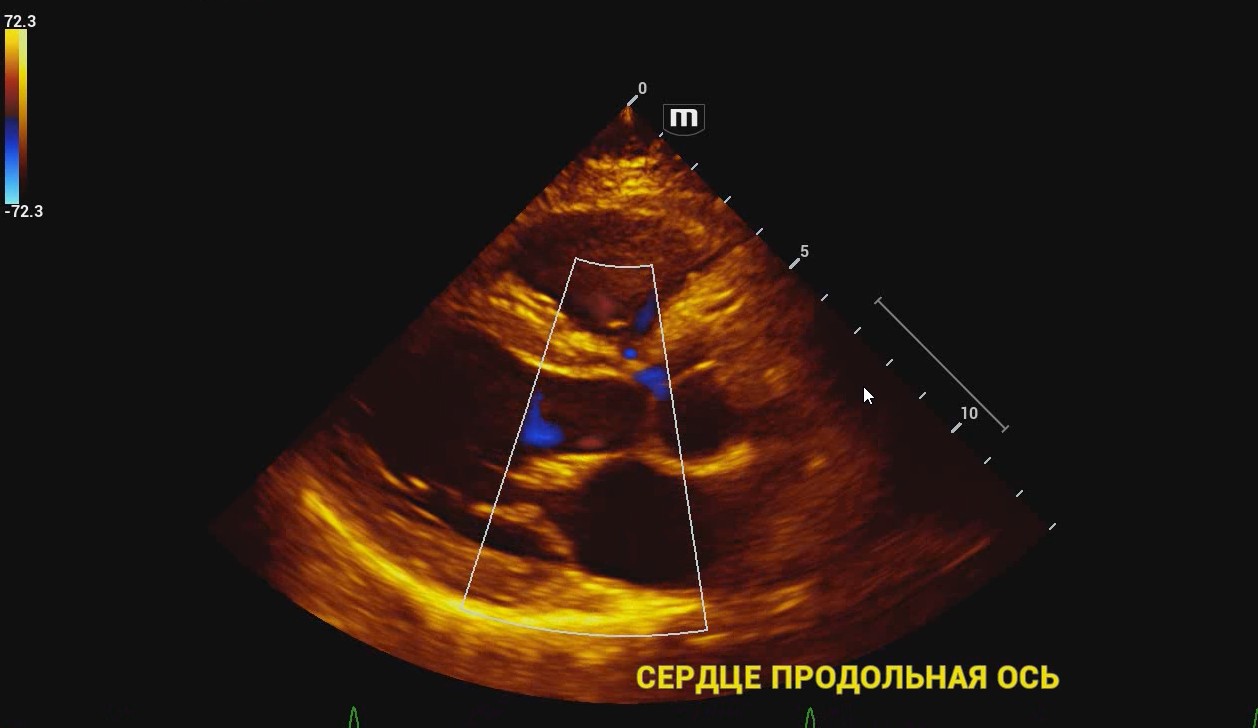

УЗИ аппарат Mindray Resona I9 – экспертный сканер в линейке производителя Mindray. Ультразвуковой аппарат поддерживает все современные технологии визуализации и протоколы расчетов для быстрого и точного проведения диагностики в разных областях медицины.

Платформа ZST+ Платформа ZST + — это уникальное инновационное решение, являющееся новой ступенью развития технологий в области ультразвуковой диагностики. В основе данной платформы - преобразование метода обработки ультразвуковых данных из традиционной в зонную, благодаря чему преодолевается традиционный компромисс между пространственным, временным разрешением и однородностью изображения ткани, что обеспечивает исключительное качество визуализации.